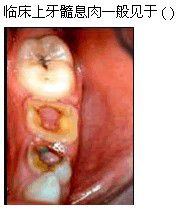

A.急性牙髓炎浆液期

B.急性牙髓炎化脓期

C.慢性闭锁性牙髓炎

D.慢性溃疡性牙髓炎

E.慢性增生性牙髓炎

[单选题]A.急性牙髓炎浆液期B.急性牙髓炎化脓期C.慢性闭锁性牙髓炎D.慢性溃疡性牙髓炎E.慢性增生性牙髓炎